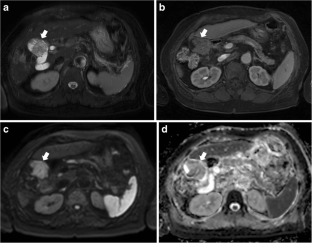

Fig. 1

Fig. 2

Fig. 3

Fig. 4

Fig. 5